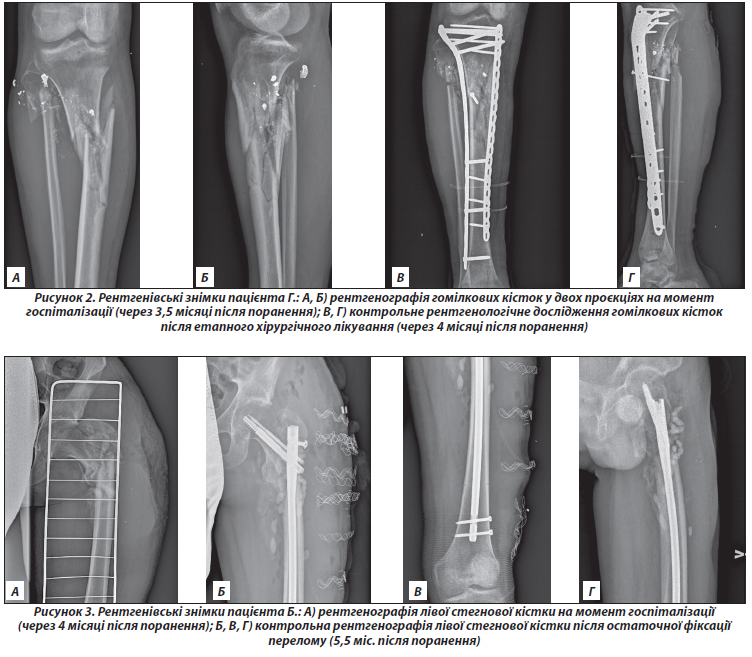

Клінічний випадок 1. Пацієнт Д., 44 роки. Стан після вогнепального кульового поранення (04.04.2022) — вогнепальний багатоуламковий перелом діафізу правої стегнової кістки зі зміщенням фрагментів. Після отримання поранення потрапив у полон, де перебував близько 3 місяців. Права кінцівка була зафіксована побратимами за допомогою підручних засобів, 3 місяці лежав, на праву кінцівку не спирався. Госпіталізований у стаціонар після звільнення з полону. Після стабілізації соматичного стану пацієнта й виконання металоостеосинтезу правої стегнової кістки (рис. 1) через 4 міс. після травми пацієнту проведене обстеження кісткової тканини.

/16.jpg)